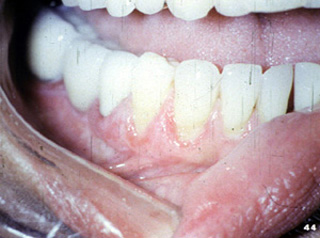

| Aquí hay

otra vista del eritema de la encía del liquen plano erosivo. |